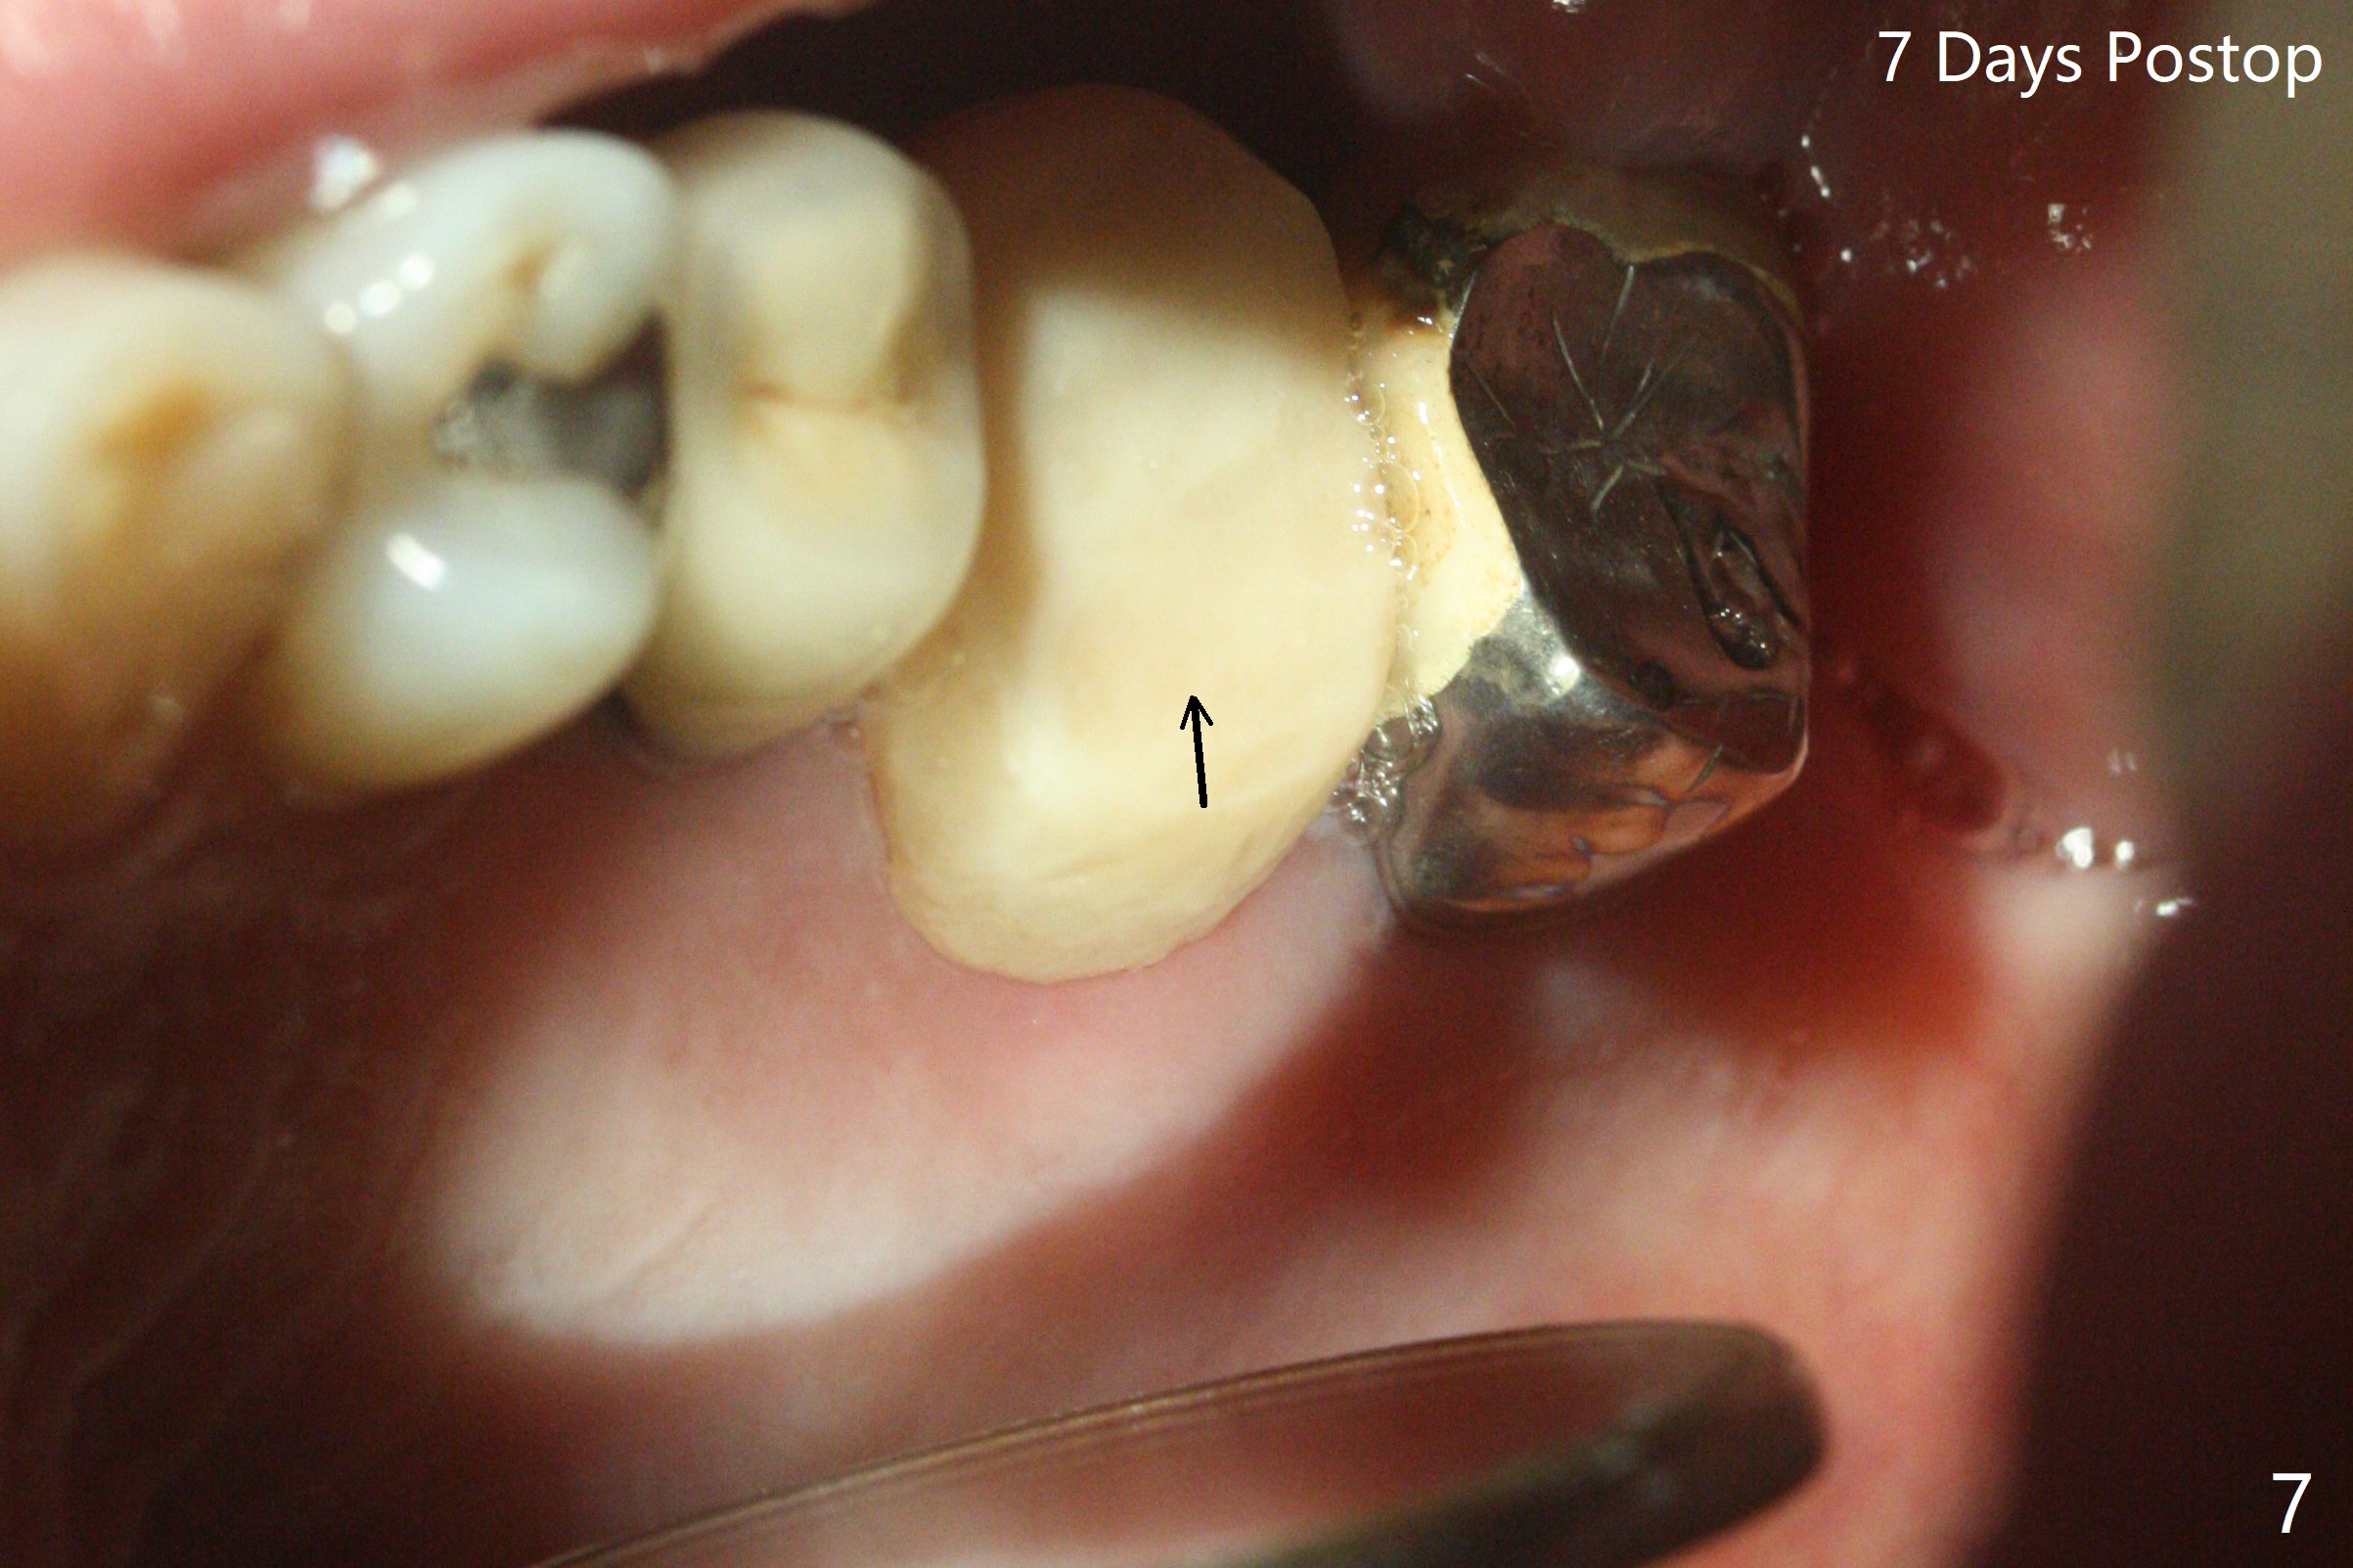

左上6腭侧退缩牙龈(图一:箭头)深部没有骨壁(图二:*),4.5x11毫米植体周围缺损(图三:*)由粘性骨粉(皮质骨,图四:*)填入,即刻临时牙冠(图五:P)覆盖腭侧缺损(空箭头)和PRF膜。临时牙冠颊腭侧做的很宽(图六),目的是关闭腭侧缺损,术后四周在不影响骨粉覆盖情况下,牙冠腭侧适当向颊侧缩小(图七:箭头),但是不应该缩短龈下边缘。术后四个月骨粉形态接近原位骨(图八),但是腭侧软硬组织仍有缺损,炎症。